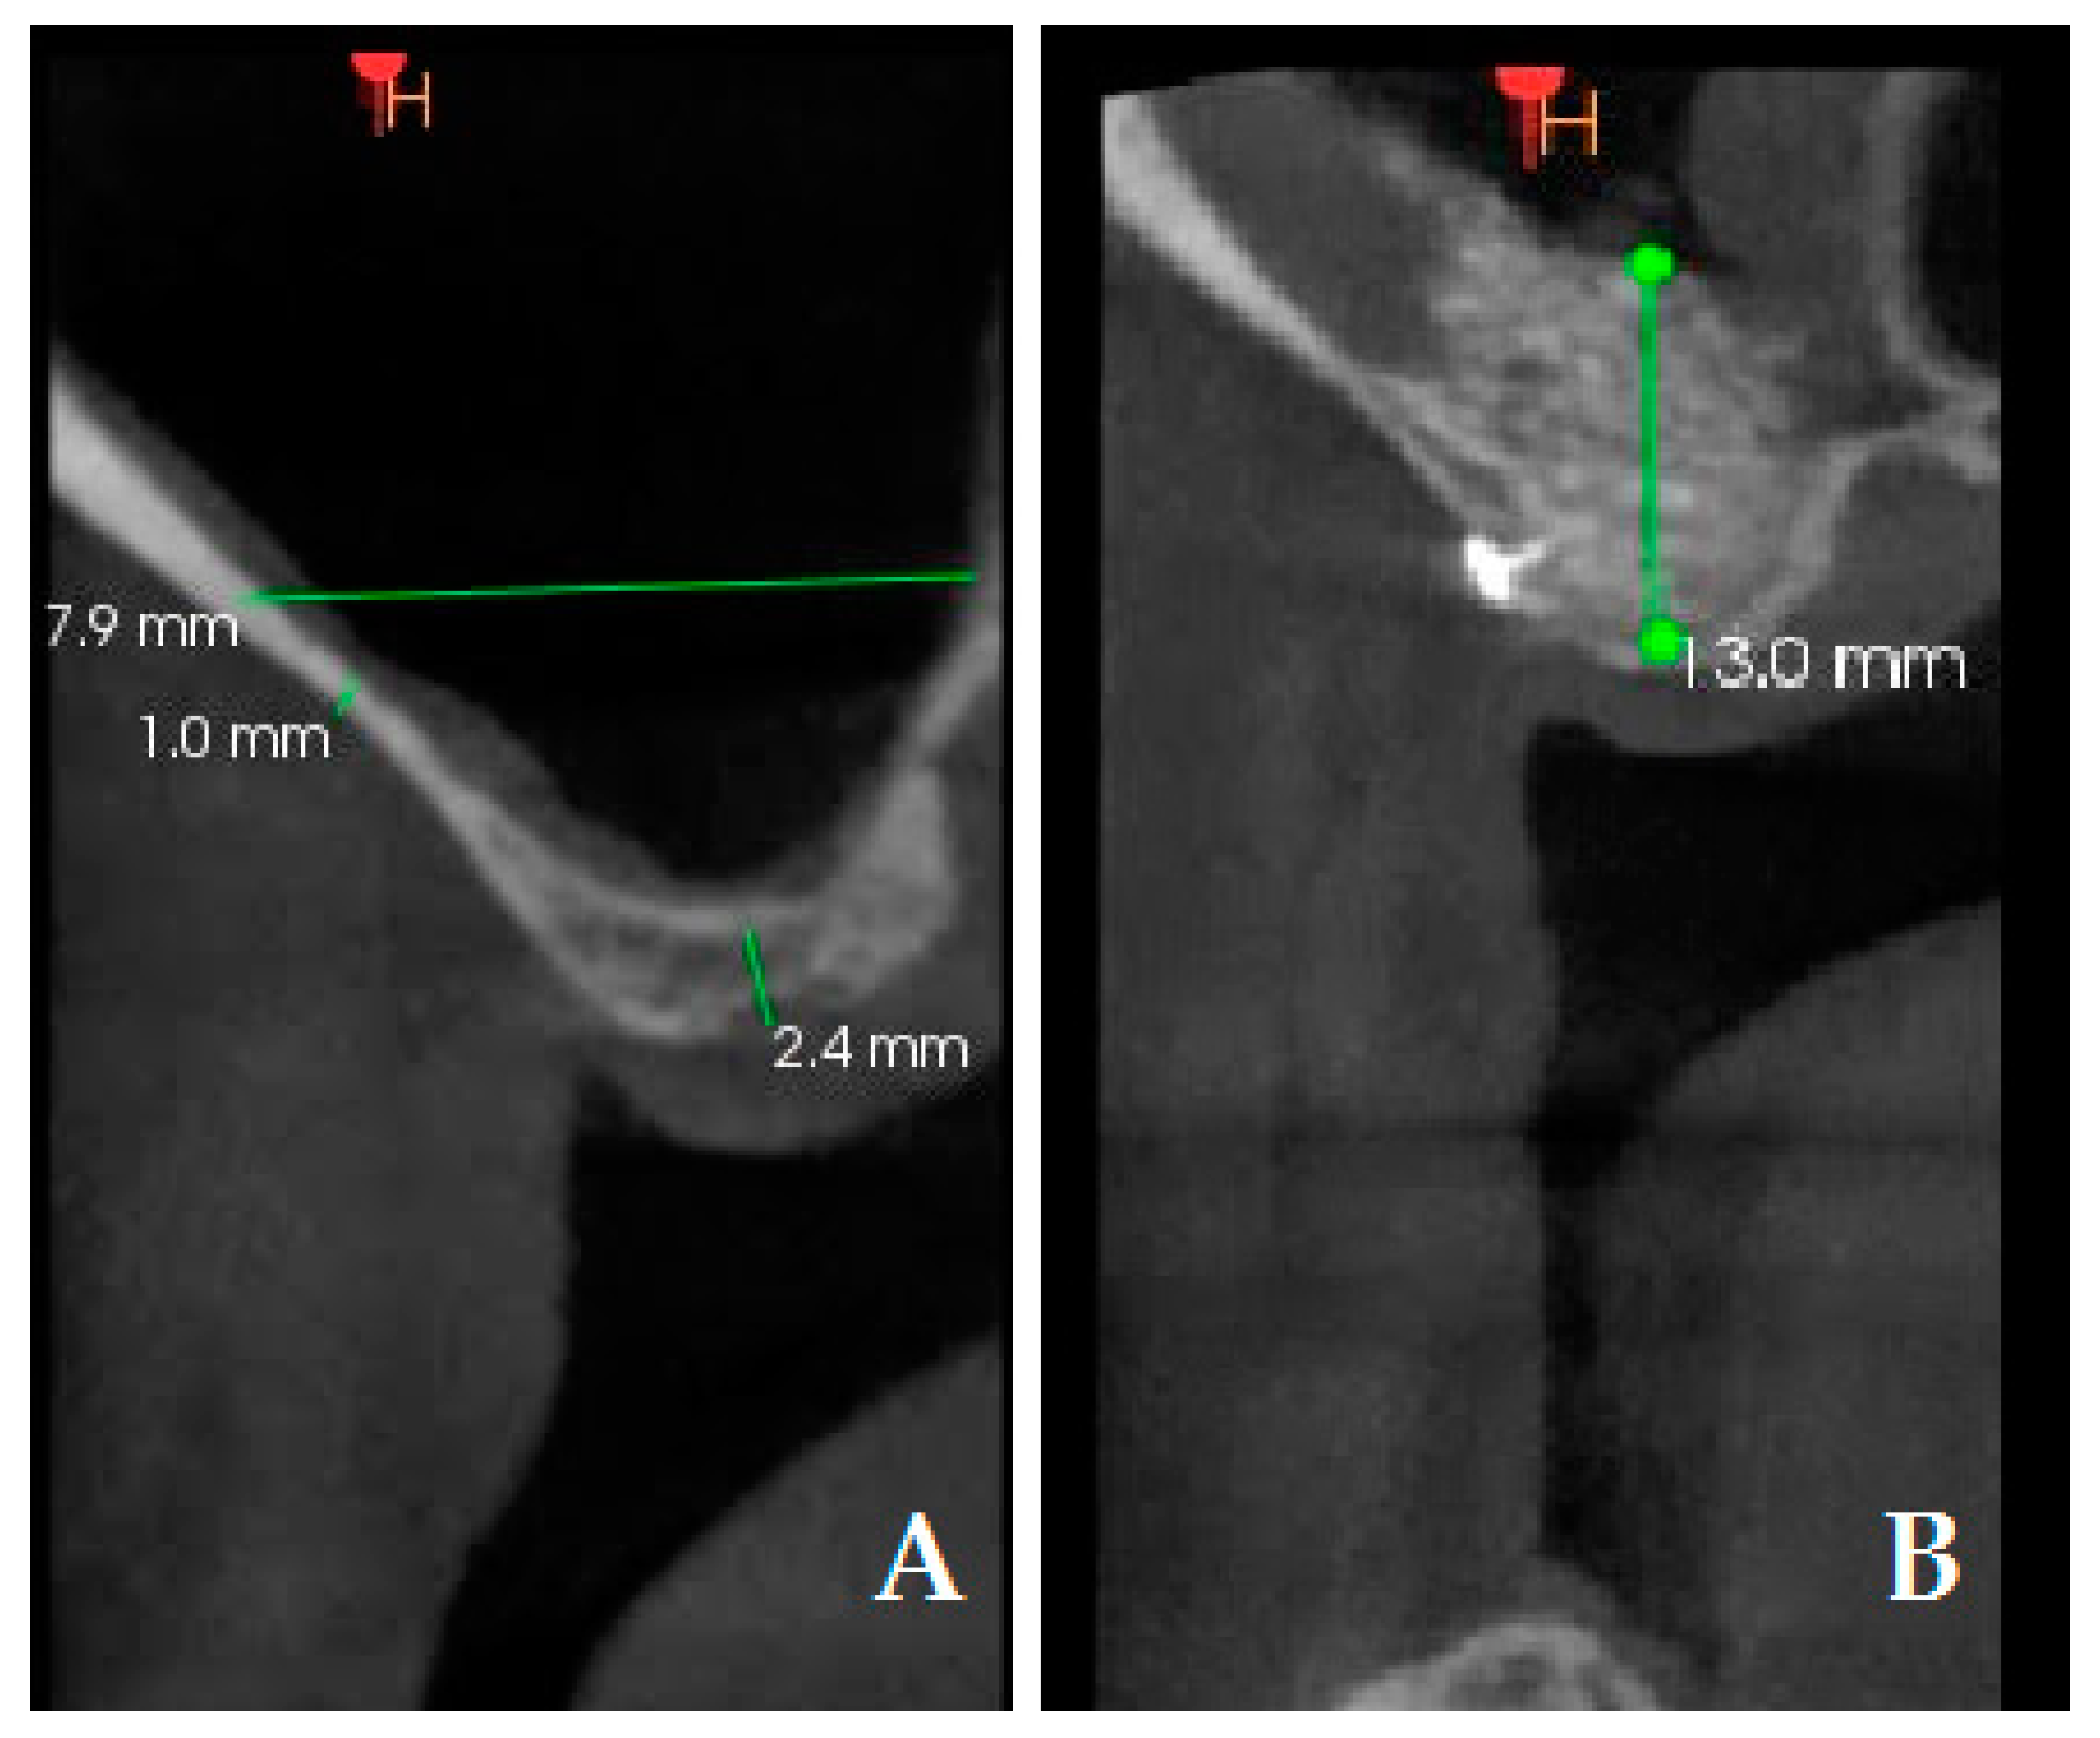

2.5. Radiographic Evaluation

| Preoperative residual bone height (mm) | Mean | 2.45 | 2.95 | 0.171 |

| Std. Err. | 0.21 | 0.30 | ||

| Std. Dev | 1.00 | 1.45 | ||

| Preoperative thickness of the lateral wall in the center (mm) | Mean | 1.38 | 1.56 | 0.130 |

| Std. Err. | 0.13 | 0.18 | ||

| Std. Dev | 0.61 | 0.87 | ||

| Bone height increment (mm) | Mean | 9.41 | 12.64 | 0.001 |

| Std. Err. | 0.31 | 0.42 | ||

| Std. Dev | 1.53 | 2.07 | ||